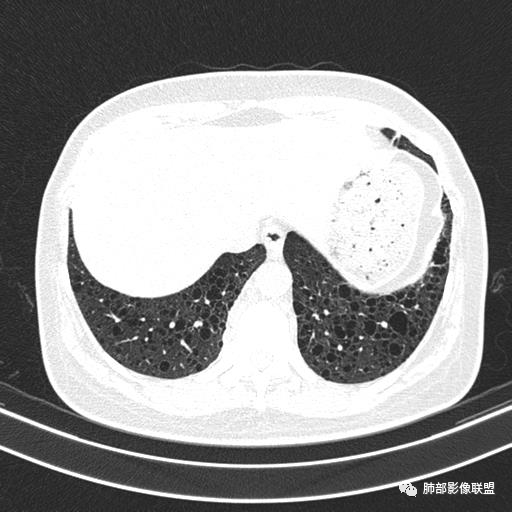

双肺弥漫囊腔,累及肋膈角,囊腔形态相对规则单一。

CT平扫示双肺弥漫分布大小不等囊状薄壁透光区,无内、中、外带分布差异,间质稍示增厚。拟LAM

中年女性育龄期妇女,咳嗽气喘,无吸烟史,有苯吸入史。影像:双肺弥漫均匀小囊腔,无明显分布优势,囊腔形态欠规则,壁薄,部分囊腔边缘血管征,伴双肺弥漫磨玻璃影,无结节,考虑lam,鉴别苯中毒肺损伤,囊腔多有分布优势,小叶中心分布为主,形态规整等

女,46,活动性气喘1年。苯吸入史半年。胸部CT:两肺弥漫囊腔,上至肺尖,下至肋膈角,形态类似小囊腔。考虑:LAM,鉴别LIP,BHD,PLCH等。

CT表现:双肺弥漫大小不等的薄壁囊腔,囊壁<2mm,外形规则,血管影多位于囊腔周围,囊腔之间肺组织正常,随着疾病进展到晚期,囊腔变大、增多,不可胜数,囊腔可融合成较大的囊,与肺气肿相似,形成间质性肺纤维化。部分病例可出现结节影。